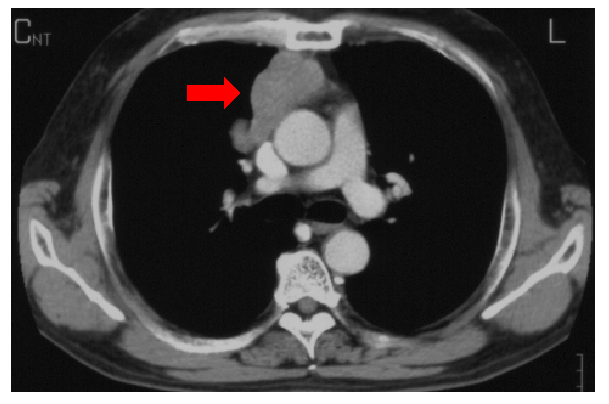

胸腺腫の胸部CT。矢印が胸腺腫の腫瘍を示しています。

横隔膜より頭側(上方)で左右の肺に挟まれた部分を縦に隔てると書いて縦隔(じゅうかく)と呼びます。そこに発生した腫瘍が縦隔腫瘍です。縦隔腫瘍には、胸腺腫、神経原性腫瘍、胚細胞腫、胸腺癌、気管支嚢胞など様々なものが含まれますが、最も多いのは胸腺腫です。胸腺は胸骨の裏、心臓の腹側の前縦隔にあり、免疫に関するリンパ球を成熟させる臓器です。成人になると退化して脂肪組織になりその働きを終えますが、胸腺腫はこの退化した胸腺の細胞から発生します。胸腺腫は肺癌と比べると悪性度の低いものが圧倒的に多いのですが、進行すると周囲の臓器に浸潤したり胸の中に散らばったり(播種)する性質を持ち、悪性腫瘍に分類されます。手術が最も治癒の期待できる治療法です。主に胸腔鏡下手術やロボット支援(ダヴィンチ)手術により1〜4つの小さな創から胸腺ごと腫瘍を摘出します。術後2〜4日の入院を要します。周囲の血管などへの浸潤が見られる場合には胸骨正中切開で手術を行います。